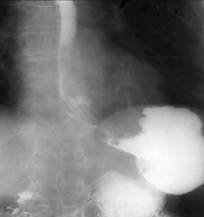

Stomacul este situat în regiunea epigastrica. Forma si pozitia lui sunt variabile. La persoanele normostenice are forma de cârlig, la cele astenice el este alungit având forma literei J sau de undita. La obezi, el este orizontalizat, în forma de corn de taur. Stomacul în cascada este format dintr-o punga superioara localizata superior si posterior care se umple cu bariu. Când aceasta este plina, bariul se revarsa în portiunea distala, asemeni apei dintr-o cascada. Uneori, când portiunea distala este umpluta, greutatea acesteia determina disparitia cascadei. Aceasta forma a stomacului este produsa de aerocolia colonului transvers, de un ulcer sau proces infiltrativ al fetei posterioare a stomacului; se poate întâlni si la obezi.